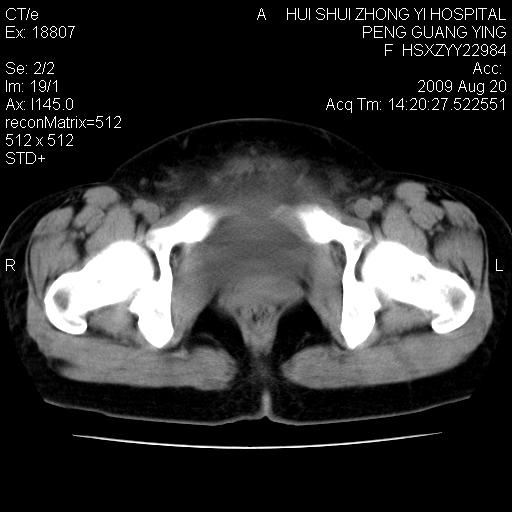

标题: CT21707:女,42岁,因发现下腹部包块2月。 [打印本页]

标题: CT21707:女,42岁,因发现下腹部包块2月。

考虑子宫肌瘤。

子宫肌瘤